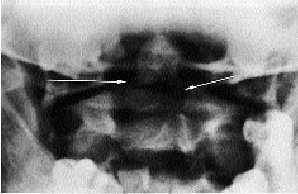

Radiología

El estudio habitual de la columna cervical, constituido por las proyecciones anteroposterior y lateral, es útil para la aproximación diagnóstica, ya que en la lateral es posible ver, de forma más o menos clara según el grado de desplazamiento, la fractura de esta apófisis de C2. Tras sospechar la fractura es preceptivo obtener una proyección específica, la transbucal de odontoides (fig. 15).

Fig. 15. Fractura de odontoides.

Con todo, el diagnóstico radiológico de esta fractura es a veces difícil, siendo necesarias las tomografías anteroposteriores de odontoides.